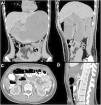

Multidetector computed tomography scan with intravenous and oral contrast (A and B), in the simple phase (C and D). A) Arterial phase, showing coronal view with important gastric distension that dissolved the contrast. B) Sagittal view, with dilatation of the first and second portion of the duodenum, with a sudden change of intestinal segment caliber. C) Axial view, showing a distance of 74 mm between the superior mesenteric artery (*) and the aorta (AA). D) Sagittal view, showing a 14 ° angle between the superior mesenteric artery (*) and the aorta (AA).

A 16-year-old female (BMI 16.8 kg/m2) sought medical attention due to epigastric abdominal pain, nausea, and vomiting of food, in addition to weight loss of 19 kg in 10 months from avoidant/restrictive food intake disorder. At hospital admission, her complete blood count, blood chemistry, and urinalysis test results showed no significant abnormalities. An abdominal CAT scan with contrast was ordered and revealed gastroduodenal distension with a transition zone at the level at the third portion of the duodenum due to compression of the superior mesenteric artery (SMA) (Fig. 1), gastric emphysema at the level of the major curvature, and portal pneumatosis (Fig. 2). A nasogastric tube was placed. Twenty-four hours after admission, endoscopy with CO2 was performed, finding subepithelial bleeding in the antrum and stomach body, with gastric necrosis, edema, and fibrin at the fundus. There was no extrinsic compression of the duodenum and a nasojejunal tube was advanced for enteral nutrition (Fig. 3). The patient was managed conservatively and had satisfactory clinical progression, tolerating oral intake at 7 days of treatment. A new CT scan was ordered that showed the absence of portal gas, and the patient was released from the hospital to undergo psychiatric and nutritional follow-up. Wilkie syndrome is caused by acute angulation of the SMA (6° to 22°) with a reduced aortomesenteric distance (2 to 8 mm) and has been associated with significant weight loss (Fig. 4). Hepatic portal venous gas is an ominous radiologic sign, associated with abdominal diseases that can be life-threatening (75% mortality). In the case described herein, gastric overdistension due to duodenal vascular compression resulted in gastric necrosis and embolization of intraluminal gas into the portal vein.